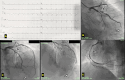

Coronary arteries are typically identified based on the myocardial territory they supply. In rare cases of coronary artery anomalies, the apex of the heart may be supplied by arteries other than the left anterior descending artery. While it is more common for the posterior descending artery from the right coronary artery to supply the apex, there are rare instances where the left circumflex (LCX) artery performs this function. This case report describes an unusual occurrence where the left ventricular apex is supplied by an obtuse marginal branch of the LCX artery. We present this case due to its rarity, unique presentation, and the challenges it poses for both medical and surgical management.